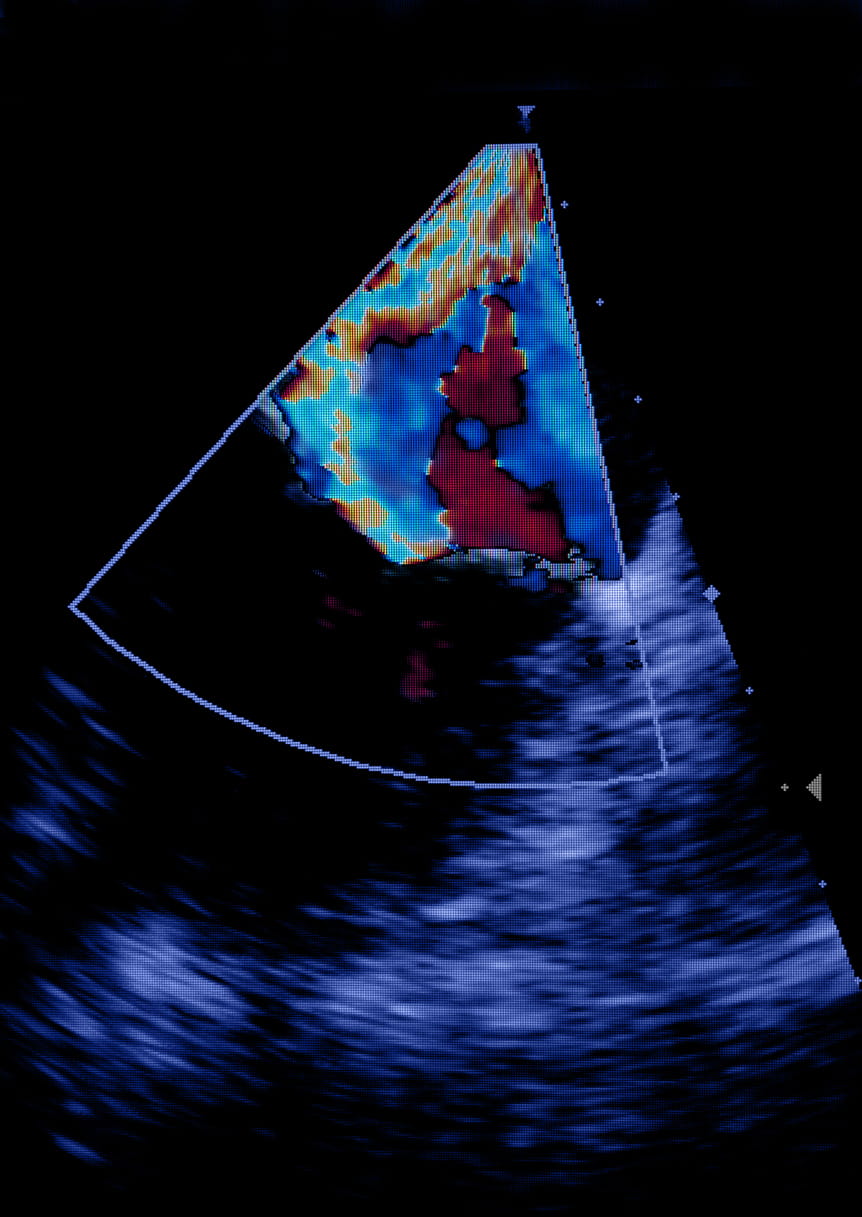

A healthy mitral valve has two flaps called leaflets that open and close with each heartbeat to keep blood flowing in one direction. When leaflets don't close sufficiently, blood can leak backward (regurgitate), forcing the heart to work much harder to pump blood throughout the body. Medication can help with symptoms but does not fix the issue, and unrepaired regurgitation can lead to severe problems such as heart failure, pulmonary hypertension or arrhythmia (irregular heartbeat).

In the operating room and with Leah asleep, the team worked together, threading a tiny, fabric-covered metal clip through a puncture in the femoral vein in Leah's leg and up to her heart using a tube called a catheter. Using ultrasound and X-ray to guide them, they positioned the clip directly at the area where the mitral valve was leaking and then released it, pinning the two leaflets together and reducing the regurgitation.